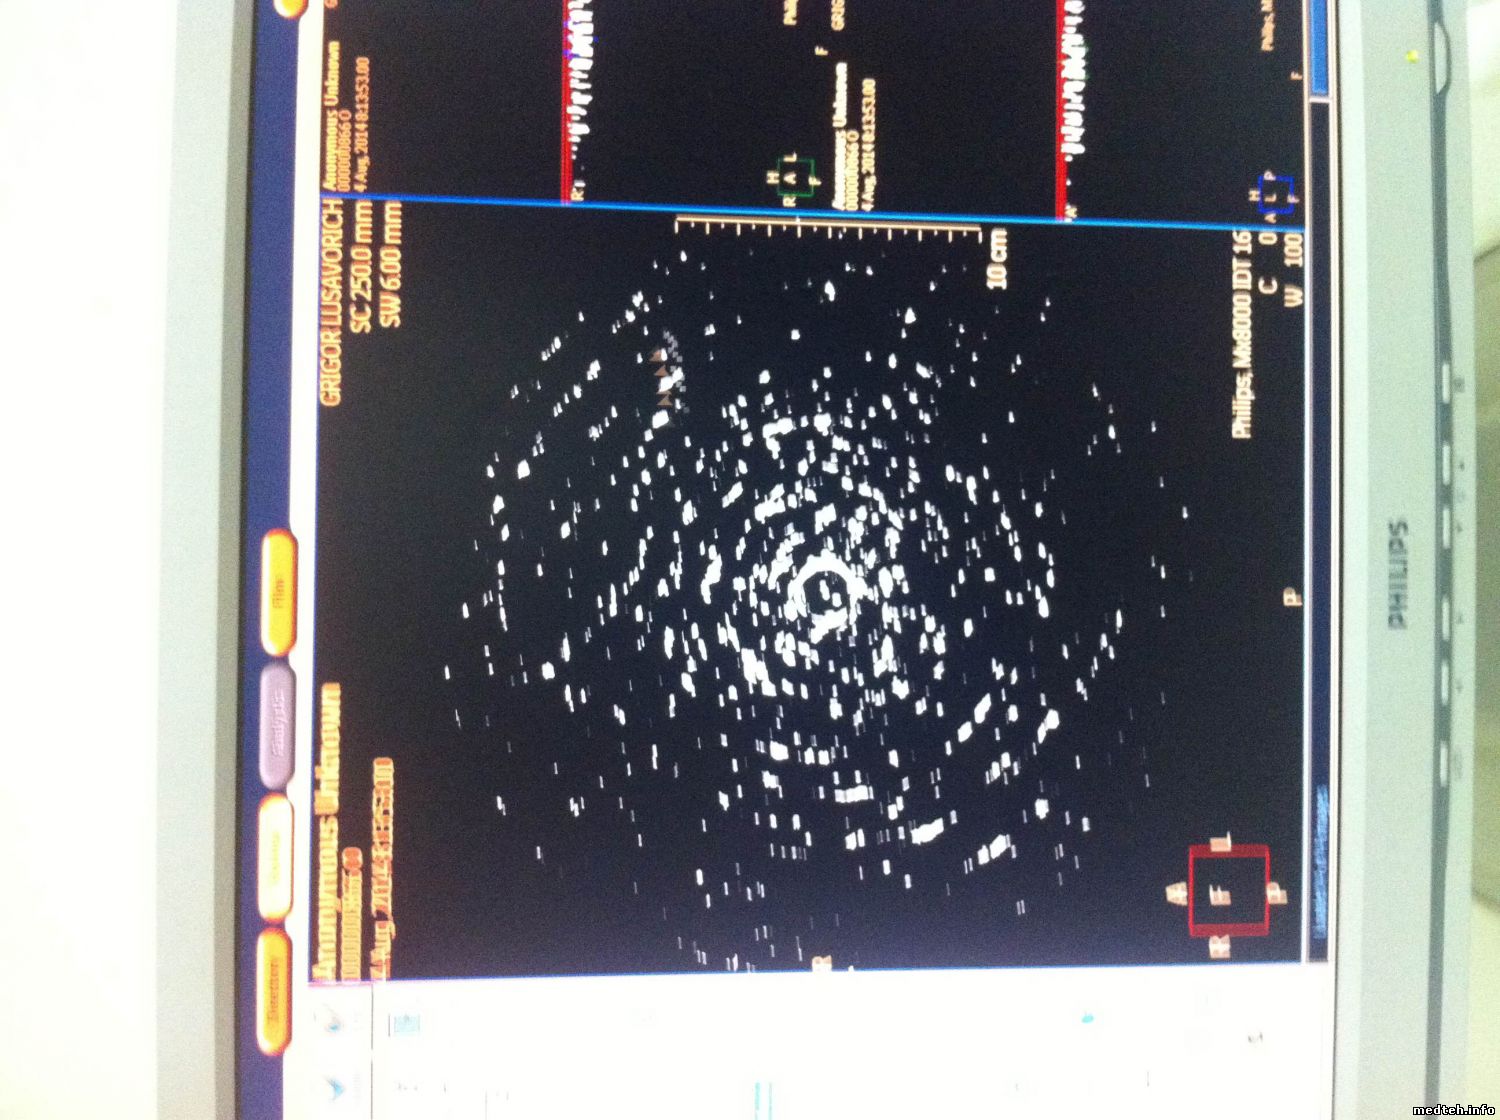

работаю с КТ Philips MX8000, вчера столкнулся с такой проблемой: После стандартной процедуре по включению аппарата на томограмме появились шумы в пол монитора, и круговые помехи на сканограме, после чего сделал калибровку по воздуху( раньше помогало ) но в этот раз не помогло а наоборот стало хуже интенсивность шумов на сканограме увеличелось, но на томограмме осталось прежнем.

вот снимки

4680378.jpg (178.3 Kb) · 5337631.jpg (196.1 Kb) · 9529230.jpg (209.1 Kb)